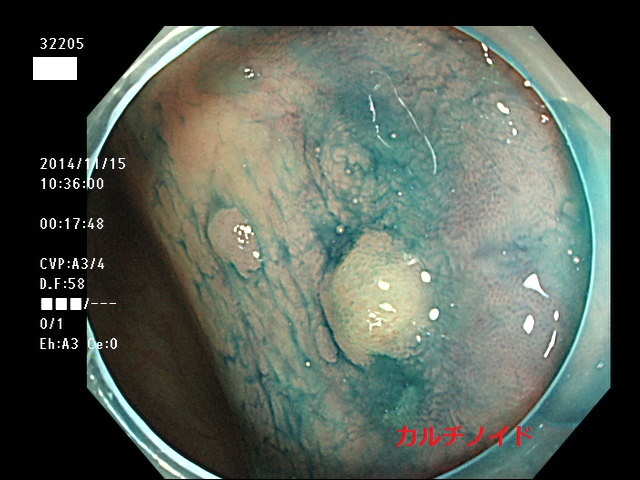

カルチノイド

上記100名より抽出した平坦・陥凹型腺腫(=癌化の危険が高いが見落としやすい病変)の内視鏡写真